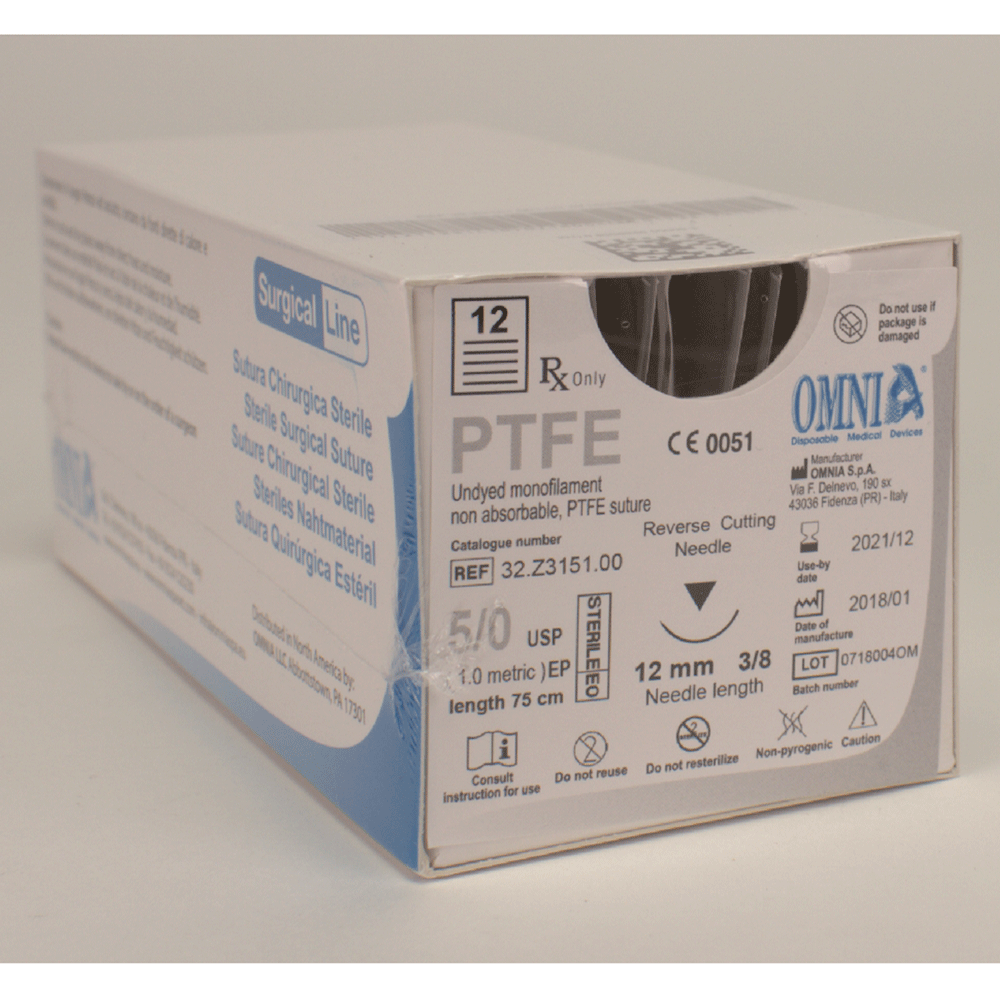

P.G.A. Suture 75 cm 7/0 Extra Cutting 10 mm 3/8 circle Extra Reverse Cutting 45

12

Ref: 32.Z3065.00€ 118,55 0 - Omnia

P.G.A. Suture 6/0 45cm Extra Sharp 12 mm 3/8 circle Extra reverse cutting 45 cm

12

Ref: 32.Z3061.00€ 116,10 0 - Omnia

PGCL Suture 4/0 75 cm. Needle: 16mm, sharp, 3/8 circle, Reverse Cutting 75 cm

12

Ref: 32.Z3300.00€ 93,74 0 - Omnia

PGCL Suture 5/0 45 cm. Needle: 12mm, extra sharp, 3/8 circle, Extra Reverse Cutt